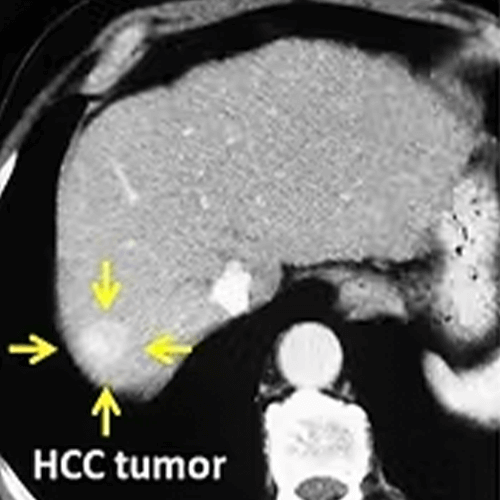

RF ablation is mostly used in liver tumors. It is the standard ablation method especially in hepatocellular carcinoma (HCC) and liver metastases.

No matter what probe is used, as with all ablation methods, the purpose of RF ablation is to destroy the tumor and a normal tissue (safety margin) of 0.5-1cm thickness around it. If this can be accomplished, the tumor is completely ablated without the need for surgery. For a successful ablation, it is important to place the RF probe correctly in the tumor. Since a single probe is usually used in RF ablation, this probe should be in the center of the tumor. Otherwise, a part of the tumor can stay alive and grow again from this area (recurrence).